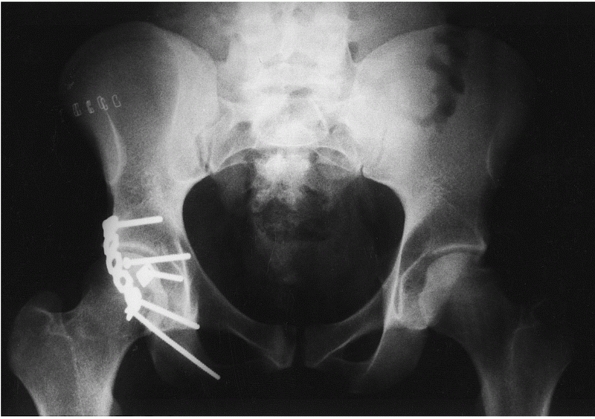

![]() |

|

FIGURE 46-27

AP radiograph of a 36-year-old who sustained a posterior hip dislocation, impaction of the femoral head, and a minimally displaced valgus femoral neck fracture in addition to type 2 anteroposterior compression pelvic injury (A). The patient was brought emergently to the operating room where the femoral neck was fixed with percutaneous screws prior to the reduction (B). After fixation, the hip was able to be reduced closed (C). At 6 months, the patient had no signs or symptoms of AVN and minor posterior pelvic pain (D). |